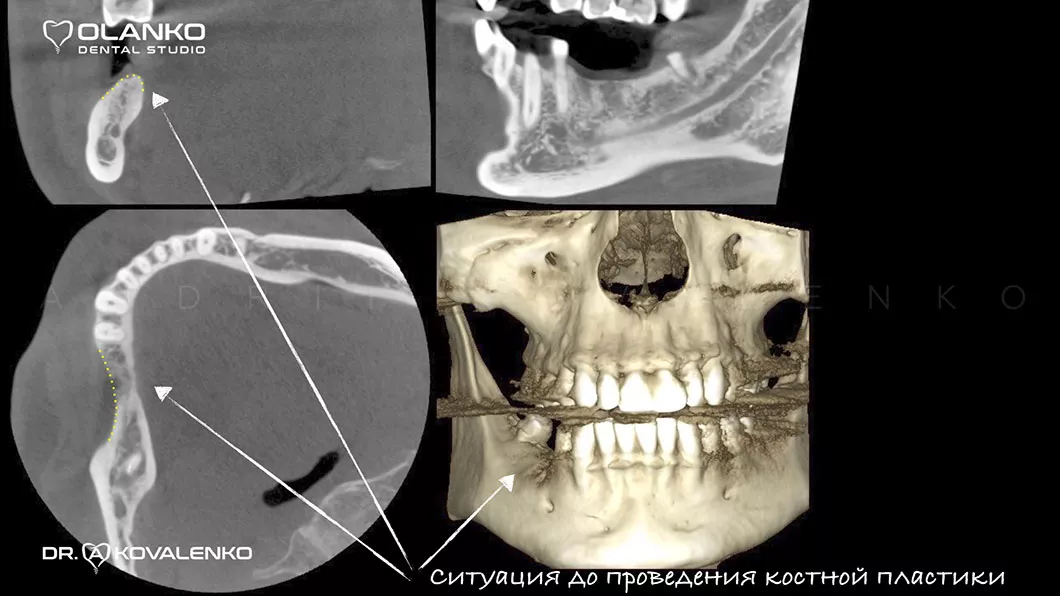

Специалисты Olanko dental studio (Оланко) г. Бровары, при выборе метода костной пластики, проводят детальный анализ компьютерной томографии и виртуально расставляют положение будущих имплантатов в специальном программном обеспечении IMPLANT STUDIO 3Shape.

В Olanko dental studio (Оланко) г. Бровары мы выполняем весь спектр операций костной пластики на верхней и нижней челюсти, а так же наращиваем костную ткань в области гайморовой пазухи (верхнечелюстного синуса).

Костная пластика методом открытого синус-лифтинга